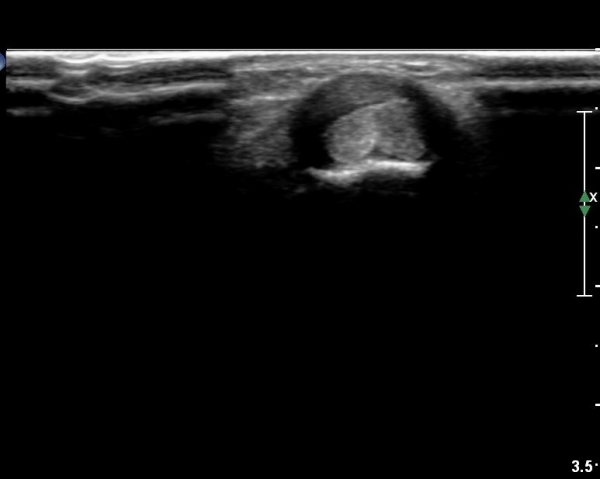

¿ä°ñ ¸»´Ü lister's tubercle ºÎÀ§¿¡¼­ Àå, ´Ü¿äÃø¼ö±Ù½ÅÀü°Ç Ⱦ´Ü¸é°Ë»ç¿¡¼­ ƯÀÌ ¼Ò°ßÀ» º¸ÀÌÁö

¾Ê´Â´Ù(»çÁø 3).